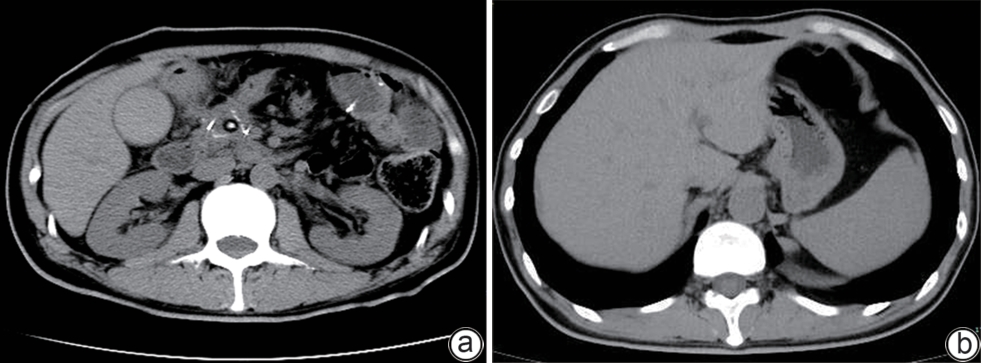

Value of internal stratification analysis of abdominal wall muscles in predicting complications after orthotopic liver transplantation

Xin SHI, Chongxiao LIANG, Bei ZHANG, Jiping WANG

2025, 41(2): 314-321. DOI: 10.12449/JCH250218

Abstract(759) HTML (355) PDF (3265KB)(57)

Abstract:

Objective  To divide the muscle into different subzones according to different density ranges using the stratified analysis on the basis of myosteatosis, and to investigate the effect of muscle density changes on complications (Clavien-Dindo grade ≥Ⅲ) after orthotopic liver transplantation (OLT).  Methods  A retrospective analysis was performed for the medical records of 145 patients who underwent OLT in The First Hospital of Jilin University from May 2013 to September 2020, and with the plain CT scan images of the largest level of lumbar 3 vertebrae of each patient as the original data, Neusoft Fatanalysis software was used to measure related muscle parameters. The independent-samples t test was used for comparison of normally distributed continuous data between two groups, and the Mann-Whitney U test was used for comparison of non-normally distributed continuous data between two groups. The chi-square test or Fisher test was for comparison of categorical data between two groups. RIAS software was used to extract clinical features and perform analysis and modeling, and three machine learning models of logistic regression (LR), support vector machine (SVM), and random forest (RFC) were constructed. The receiver operating characteristic (ROC) curve, the calibration curve, and the decision curve were plotted for each model to calculate the area under the ROC curve (AUC), sensitivity, specificity, precision, F1 score, and accuracy.  Results  The three machine learning models of LR-C, SVM-C, and RFC-C were established based on the 7 clinical features before muscle stratification analysis, among which the RFC-C model had an AUC of 0.803, a sensitivity of 0.588, and a specificity of 0.778 in the test set. Among the models of LR-CS, SVM-CS, and RFC-CS established based on the 16 clinical features after muscle stratification analysis, the LR-CS and SVM-CS models had an AUC of 0.852 in the test set, with a sensitivity of 0.765 and 0.706, respectively, and a specificity of 0.889 and 0.926, respectively. Comparison of the AUC, sensitivity, specificity, precision, F1 score, and accuracy of each model in the test set before and after muscle stratification analysis showed that there were improvements in the parameters of the predictive model after muscle stratification analysis. Comparison of the decision curves and calibration curves of each predictive model showed that the LR-CS and SVM-CS models had good efficacy in predicting postoperative complications (Clavien-Dindo grade≥Ⅲ) in OLT patients.  Conclusion  On the basis of myosteatosis, the division of the muscle into different subzones according to different densities using the stratified analysis has a certain value in predicting postoperative complications in patients with OLT.